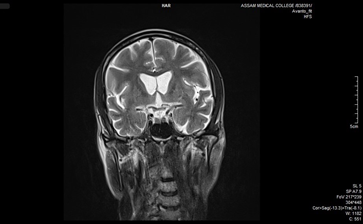

On examination, the patient showed chorea involving the face, limbs, and trunk, along with speech and gait abnormalities. MRI findings showed bilateral caudate nucleus atrophy and ventricular enlargement. Genetic testing confirmed 41 CAG repeats in one allele.

3. MRI (Coronal T2) confirming striatal changes

Figure 3. MRI brain (T2 weighted coronal section) shows head of bilateral caudate nuclei with mild atrophied ex-vacou mid dilatation.